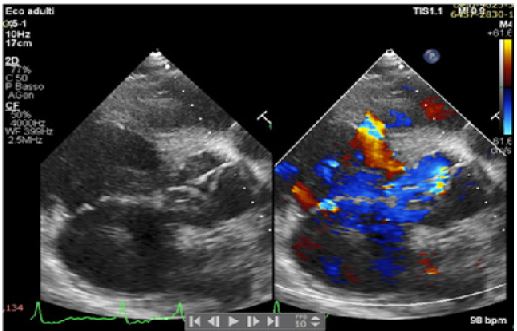

A 42-years old Senegalese man was referred to our department for dyspnea on exertion (NYHA II-III) and clinical signs of heart failure. In his clinical history an undefined cardiopathy, known since childhood but not investigated because asymptomatic, was reported. General examination revealed tachyarrhythmic pulse (rate of 103 per minute) along with normal blood pressure (130/65 mmHg) and arterial oxygen saturation (SpO2 97-99%). Electrocardiography demonstrated atrial fibrillation with left ventricular hypertrophy and signs of pressure overload (Figure 1), while chest X-Ray showed severe cardiomegaly and pulmonary congestion. Transthoracic Echocardiogram (TTE) with color Doppler revealed the presence of a 21 mm perimembranosus Ventricular Septal Defect (VSD), below the aortic valve, with relevant left-to-right shunt (gradient 90 mmHg), partially closed by prolapsing right coronary cusp and accessory tricuspid valve tissue (Figures 2 and 3). A hypertrophied muscle bundle in the mid-ventricular region of the Right Ventricle (RV) along with color-flow turbulence was documented (Figure 4). Due to misalignment, no accurate estimation of intraventricular RV pressure was feasible, but moderate tricuspid regurgitation revealed an atrioventricular gradient of 70 mmHg, suggesting high RV pressures. Other findings were severe aortic valve regurgitation with severe dilation of ascending aorta (diameters of sinuses of Valsalva 60 mm, 28 mm/m2, z-score +6,3, tubular ascending aorta 48 mm, 23 mm/m2, z-score +5,7). 2D and 3 D Transoesophageal Echocardiographic Examination (TOE) confirmed the presence of the anomalous muscle band dividing the RV into two parts: a high-pressure inlet portion and a lower pressure outlet portion (Figures 5 and 6). Severe dilation of both aorta and pulmonary trunk was revealed, confirming severe aortic valve regurgitation with multiple jets and determined by different factors (lack of coaptation, prolapse of the right cusp and distortion of the noncoronary cusp). To accurately measure RV pressures cardiac catheterization was performed. The systolic pressure of the right ventricular inlet and the outlet pressure were 78 and 38 mmHg respectively, determing an intraventricular gradient of 40 mmHg. There was no pressure gradient between the right ventricle outlet tract and the main pulmonary artery (systolic/diastolic/mean pressures were 38/18/25 mmHg respectively). Normal coronary arteries were documented. Patient was scheduled for corrective surgery in the form of resection of the anomalous muscle bundle along with patch closure of the VSD and Bentall procedure for ascending aorta or aortic valve replacement.

Figure 2: Parasternal long axis.

Figure 3: Parasternal long axis.